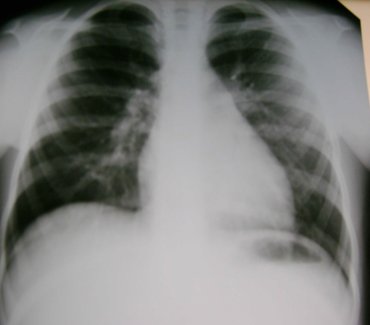

Сережа Х. 8 лет – поступил 9.10.08 – на 7-й день с Т0 390. кашлем без катаральных явлений Дома не лечился

При поступлении: катара нет, справа ослабление дыхания, пучки крепитирующих хрипов Кровь: Л–10,8 тыс, с/я 62%, СОЭ 30, СРБ 50 мг/л

КЛИНИЧЕСКИЙ СЛУЧАЙ (IV)

13.10.08